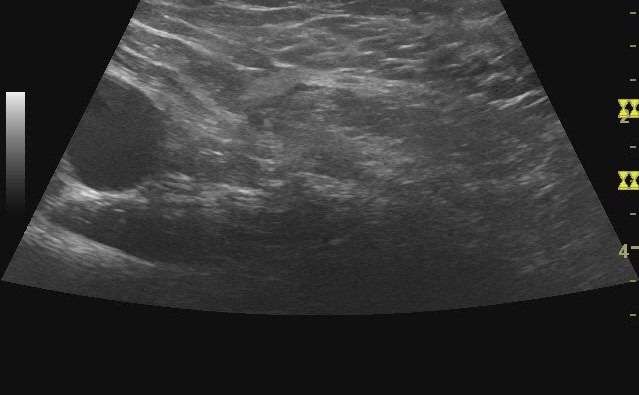

Μέσω του Υπερηχογραφήματος Κοιλιακού Τοιχώματος, ένας εξειδικευμένος Ιατρός-Ακτινολόγος μπορεί να προχωρήσει σε διάγνωση πολλών καταστάσεων που πιθανώς να πλήττουν το κοιλιακό τοίχωμα, όπως:

- Εστιακές Αλλοιώσεις

- Δυναμική Εξέταση: Το Υπερηχογράφημα αποτελεί μία δυναμική μέθοδο απεικόνισης, κάτι που σημαίνει ότι η εξέταση μπορεί να γίνει κατά τη διάρκεια της κίνησης. Αυτή η δυνατότητα είναι ιδιαίτερα χρήσιμη στη μελέτη του κοιλιακού τοιχώματος, καθώς όταν το κοιλιακό τοίχωμα βρίσκεται σε ηρεμία, οι κήλες μπορεί να μην είναι εμφανείς. Με τη δυναμική δοκιμασία Valsalva, είναι δυνατή η διάγνωση μηροκήλης, βουβωνοκήλης ή ομφαλοκήλης.